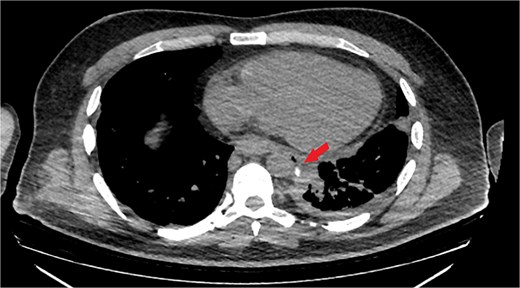

The patient was diagnosed with EP. Gastroscopy showed a 2 cm tear at 27–28 cm from the incisors and erosive esophagitis at the gastroesophageal junction (GEJ). Chest CT confirmed pneumomediastinum, subcutaneous emphysema, pleural effusion, and aspiration pneumonia (Fig. 2). The patient was transferred to the SICU for intensive monitoring. On Day 2, a right thoracotomy was performed, revealing a linear esophageal tear, food collection (mainly red meat), and a 1 cm through-and-through perforation. The procedure included debridement, defect repair with pleural patch reinforcement, and chest tube placement. The patient was monitored postoperatively in the SICU. On Day 4, the patient was extubated, and gastroscopy on Day 10 confirmed healing. An esophageal stent was placed on Day 11, with gradual clinical improvement and tolerance of oral fluids. Chest tubes were transitioned to water-seal drainage. Recurrent stent migrations occurred on Days 15, 17, and 19, requiring repositioning and eventual removal. On Day 20, bronchoscopy identified a broncho-esophageal fistula, and chest CT showed reduced leakage (Fig. 3). The patient was kept nothing by mouth (NPO) for further healing.

Chest CT scan: (a) with IV contrast, extensive pneumomediastinum as well as extensive cervical and anterior chest subcutaneous surgical emphysema with mild bilateral pleural effusion. (b) IV and oral contrast: Evidence contrast leakage arising from the left posterolateral aspect of mid esophagus associated with mild left loculated pleural effusion and mild pneumomediastinum.